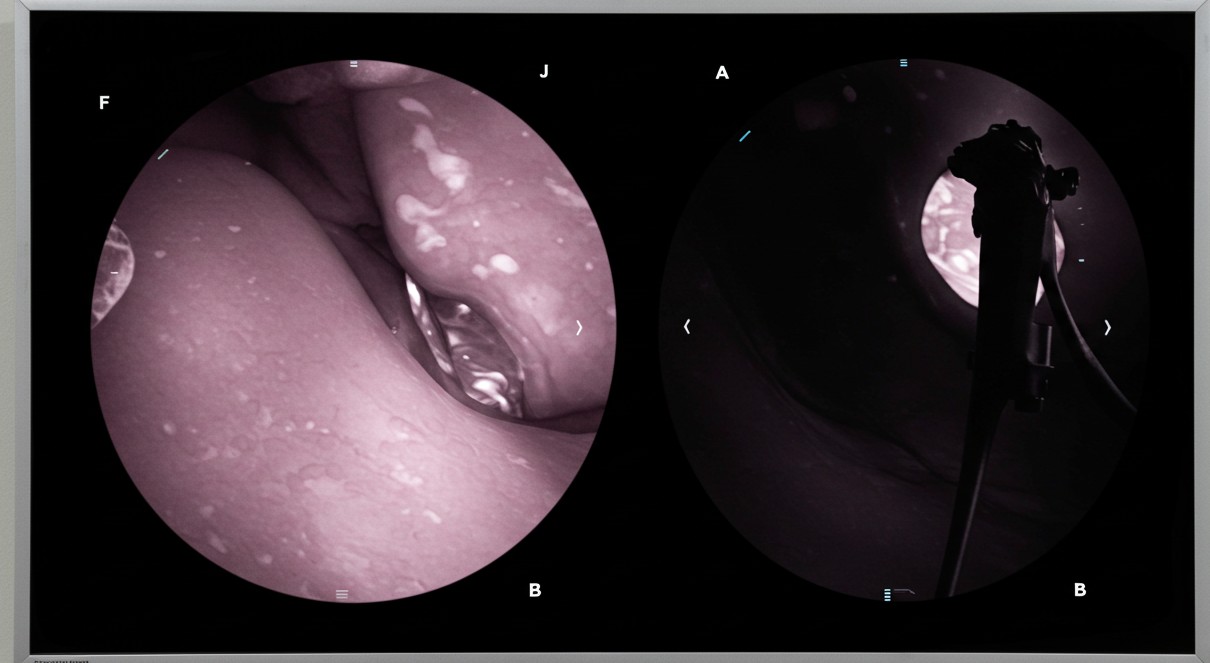

• 검진 방법: 위내시경 권고 (기본 검진 방법으로 확정)

이는 위내시경이 조기 위암 발견에 가장 효과적이라는 국내외 연구 결과를 반영한 것입니다.